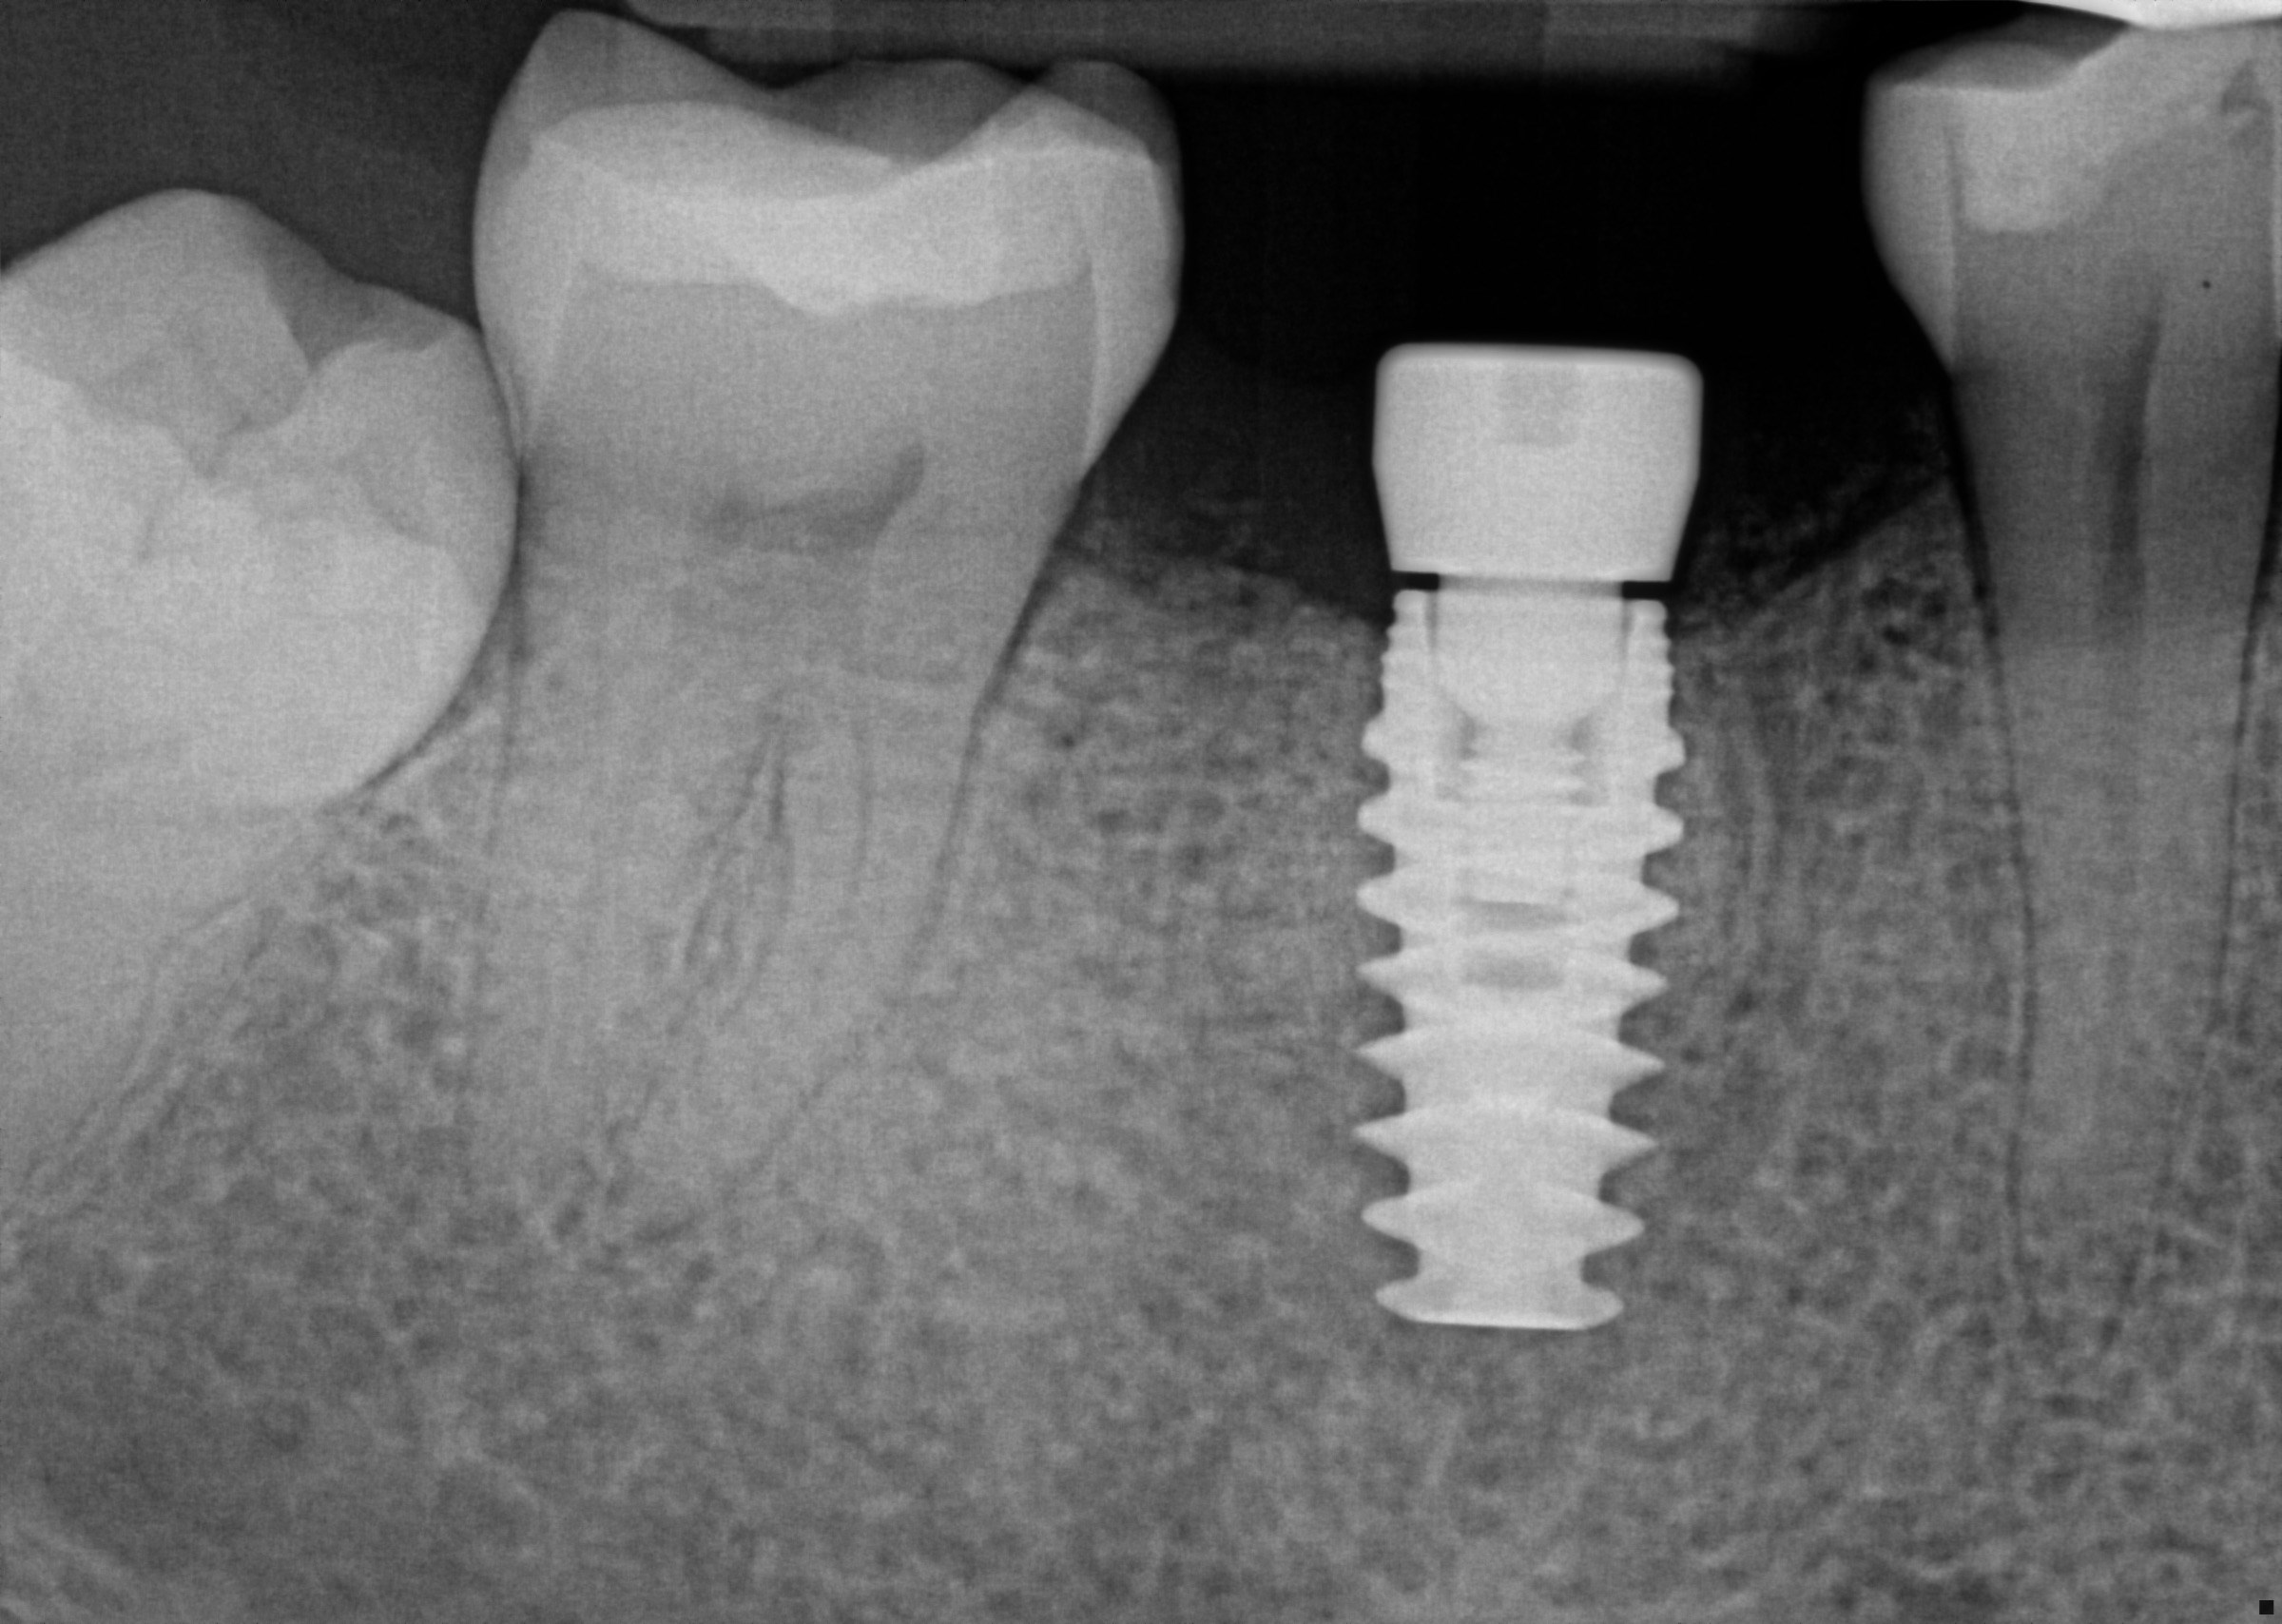

Custom Implant Crown

Procedure Details